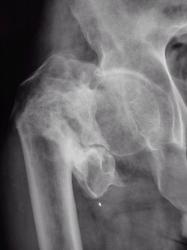

Травма. Пациент направлен врачом хирургом на рентгенографию плечевого сустава.

Спиральный перелом со смещением. А что в локтевом суставе? Мне кажется, что спираль продолжается дистальнее.

А что по "поводу головки" плечевой кости в "районе большого бугорка".

Думаю, что это начало спирали.

А еще это похоже на перелом по типу Хилл-Сакса большого бугорка.

Мне кажется, что импрессионного перелома бугорка (повреждение Хилл-Сакса) здесь нет. При данном повреждении импрессия более выражена. Типичный перелом Хилл-Сакса выглядит примерно так.

Хотя, конечно, аксиальная проекция всё бы расставила по своим местам. На мой взгляд, второго перелома в области бугорка здесь нет.